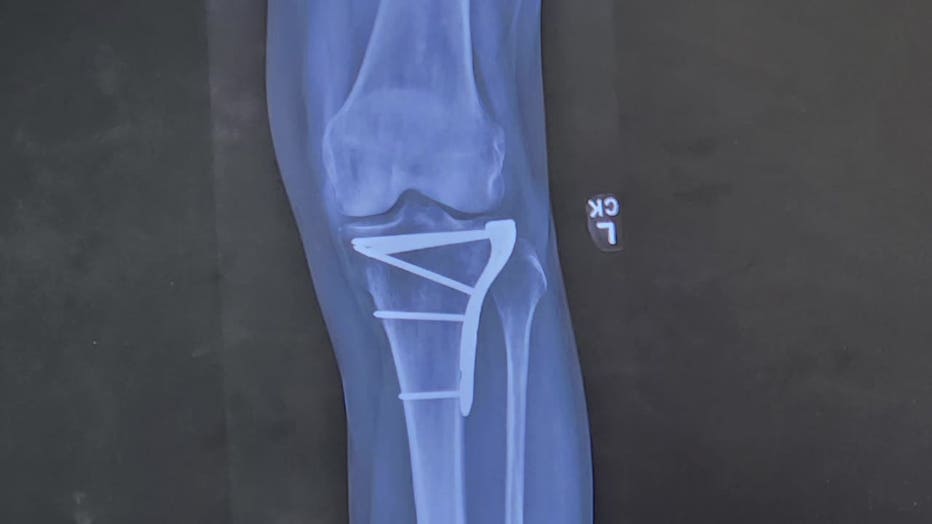

Back in July, a friend's rottweiler rammed into Staral's leg, breaking her tibia just below the knee joint.

Four difficult days later, Staral rolled out of surgery at MOSH in Franklin with a plate in her knee.